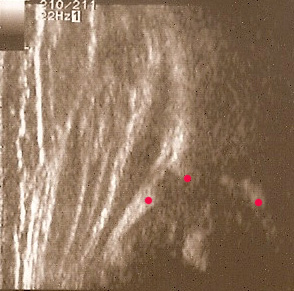

typ I czerwone kropki(od lewej) pokazują punkty do kreślenia 1 środek geometryczny obrąbka 2.brzeg kostny;3.gałąż dolną kości biodrowej